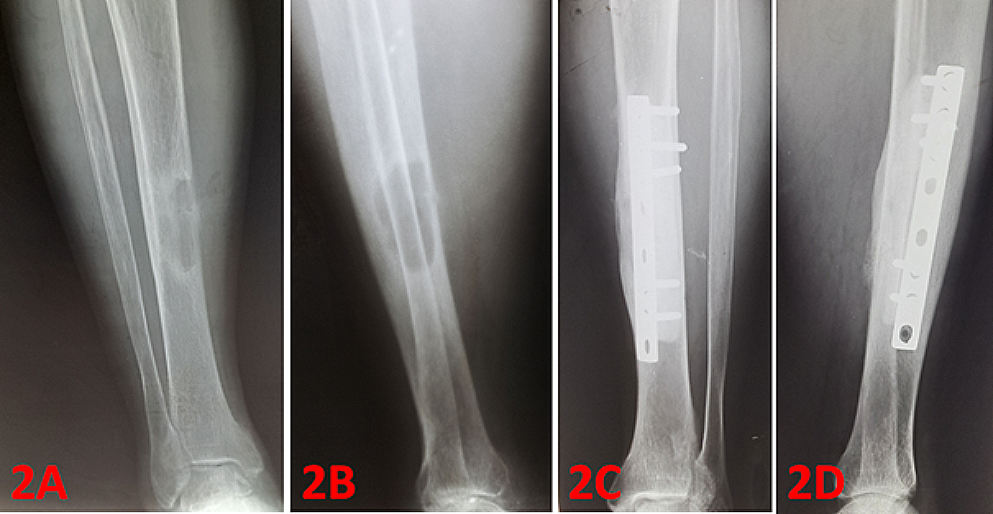

Fig. 2

A 47-year-old male with brown tumor in the right tibial diaphysis (2 A and 2B: preoperative radiograms). Curettage and cementing was applied, followed by fixation was perfomed by using DCP plate. Figure 2 C and 2D shows postoperative 48th months radiograms

The most common sites of localization were the pelvis, femur, ribs, tibia, proximal humerus, and mandible (Table 2). 7 patients (26,9%) had solitary lesions, while 19 patients (73,1%) had multiple lesions. A total of 65 lesions were observed in 26 patients. Orthopedic surgery was performed in 21 of 26 patients, the other 5 cases were followed up conservatively. Among the 65 lesions, 23 lesions (35,4%) underwent surgery, whereas 42 lesions (64,6%) were followed conservatively (Table 2). Intralesional curettage was performed in 19 cases (82,6%). The resulting cavity was filled with bone cement in 11 cases (47,8%). Bone grafting was applied in 8 cases (34,8%) (see Figs. 1, 2; Table 3).